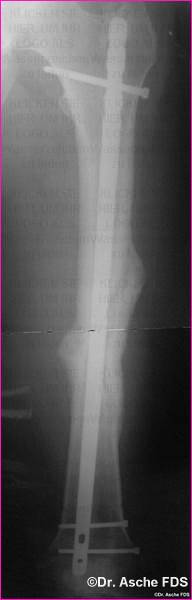

Die unten beschriebene Art der Valgisierung- und Drehosteotomie

wurde vorgenommen.

Die Stabilisierung erfolget mit einem Kompressionsnagel

T2

Nach 3 Monaten war die Fraktur fest verheilt, der Patient

konnte beschwerdefrei laufen

Drehung und Achse waren Korrekt. Auch bei Drehfehlern

von 10° sollte immer wieder die Frage einer Korrektur erwogen werden.